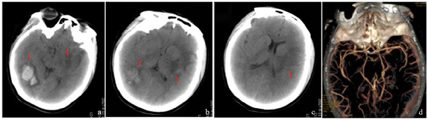

入院后予以头孢曲松抗感染、脱水降低颅内压力、保护脑组织、营养支持等对症处理。入院后第2天患者体温降至正常。第5天,患者再次出现发热,抗生素更换为头孢哌酮钠舒巴坦钠,患者仍偶有低热。第10天,患者诉胸部不适,再次详细体格检查发现胸骨左缘可闻及3~4/6级收缩期吹风样杂音。进一步完善经食道心脏彩色超声检查(图3):(1)主动脉瓣赘生物形成并主动脉瓣中重度反流,符合细菌性心内膜炎;(2)二叶式主动脉瓣。血培养提示粪肠球菌阳性。抗生素调整为青霉素+阿米卡星。9月30日,患者突然出现左侧下腹部疼痛、腹胀。查全腹增强CT:脾梗死、左侧肾梗死。腹部CT血管成像未见异常。10月11日后患者未再发热。10月16日,血培养阴性。10月24日,患者行心脏瓣膜置换术。2个月后随访,患者可自行缓慢行走,右手精细活动差。一年半后随访,患者未出现血管栓塞事件。